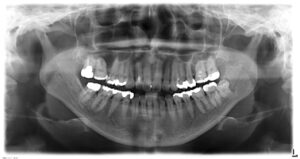

40歳男性の二次虫歯を顕微鏡根管治療